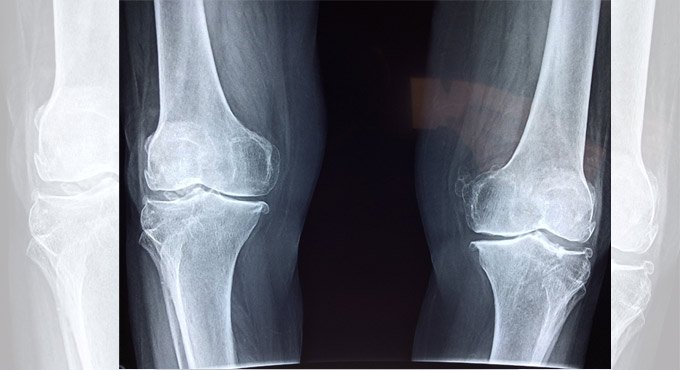

Toronto: An underused type of knee surgery in younger patients shows considerable success in reducing the need for total knee replacement, a new study suggests.

The surgery, named high tibial osteotomy, is a knee surgery aimed at younger patients in the earlier stages of knee osteoarthritis, according to the study published in CMAJ (Canadian Medical Association Journal).

Knee osteoarthritis is a common cause of pain and disability and puts tremendous burden on health care systems. Total knee replacement is frequently performed on older patients with end-stage disease and limited mobility.

Of the patients in this study getting high tibial osteotomy (643 knees in 556 patients), 95 per cent did not need a total knee replacement within 5 years, and 79 per cent did not get a total knee replacement within 10 years.

Even in patients traditionally not considered ideal candidates for high tibial osteotomy (e.g., women and patients with later-stage disease), about 70 per cent did not get a knee replacement within 10 years.

The procedure is particularly suitable for people who are younger, have less severe joint damage and who may be more physically active.